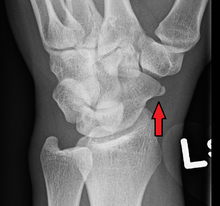

A subtle scaphoid fracture